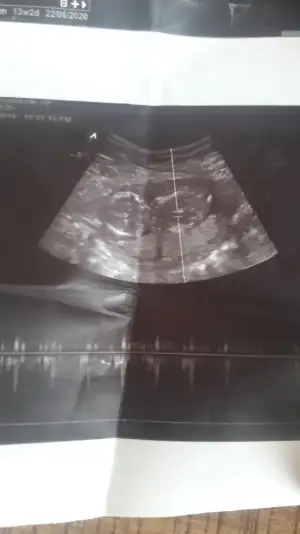

Kız gibi gibi sanki eminde değilim başka usg varmıArkadaşlar 13 haftalık yorumlarınızı bekliyorum çatladımmmmm![]()

Evet var onuda atatum hemenKız gibi gibi sanki eminde değilim başka usg varmı

Yok cnm net degil bu usg daha pusluEvet var onuda atatum hemen![]()